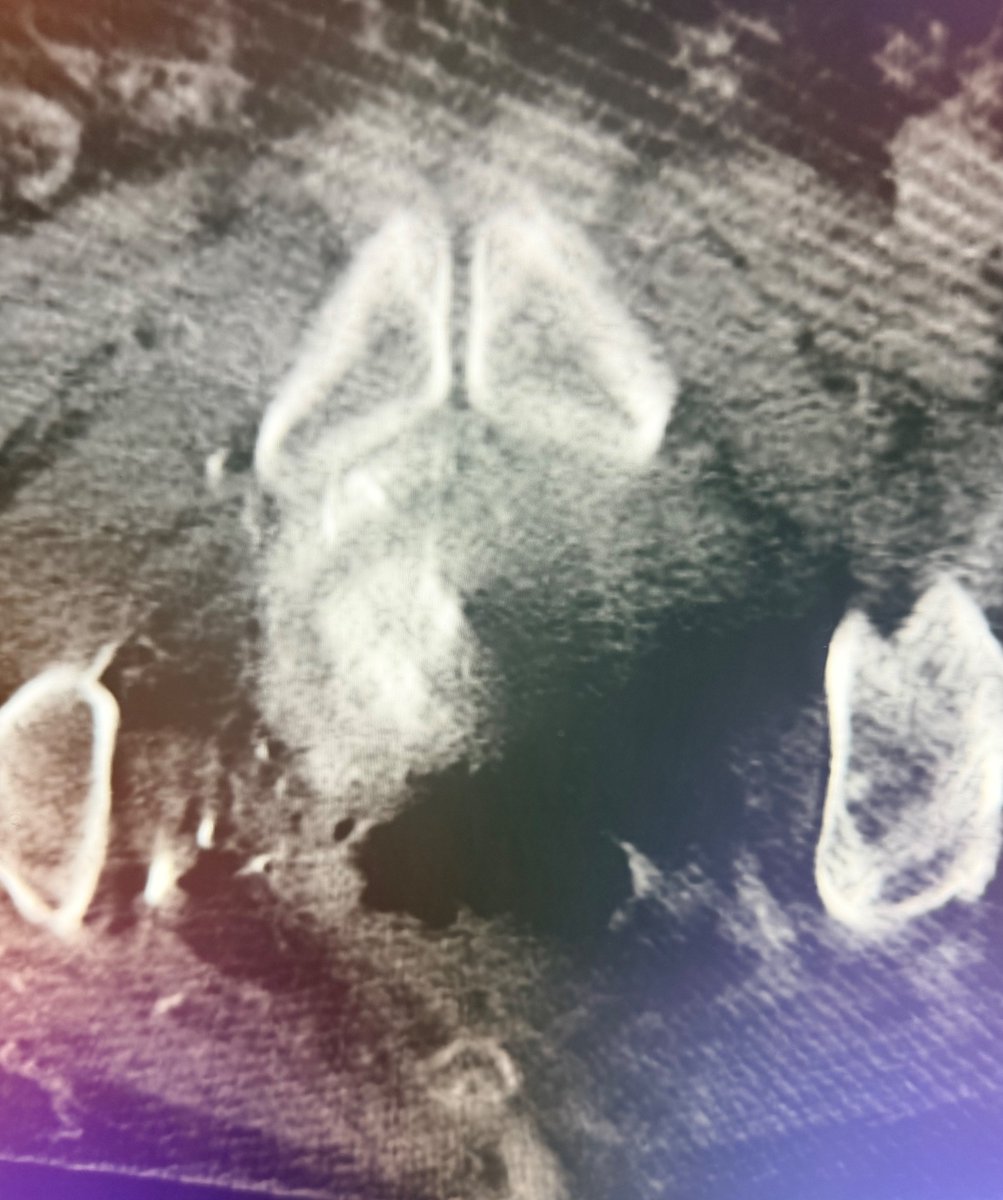

A patient with IVC atresia rolled into my office in a wheelchair. No options were offered for years. Successful IVC reconstruction. One week later, walked into my office for followup! One month later, living his best life, no pain and no limitations. #chogazi #irad #vascular #cardiotwitter @SIRRFS @SIR_ECS @SIRspecialists @VascularSVS @farkomd @AmputationSuck @ChengaziMD